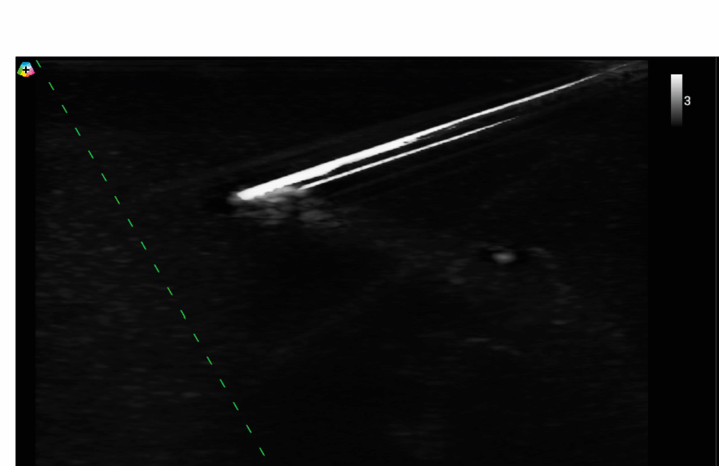

Większa kontrola nad igłą podczas zabiegu

Funkcja wizualizacji igły pozwala prowadzić ją dokładnie w osi naczynia, co skraca czas wkłucia i redukuje ryzyko niepowodzeń i powikłań.

potwierdzona funkcja wizualizacji igły (ENV);

Zobacz, jak mobilne USG BenQ T3300 wspiera codzienną praktykę kliniczną

A: T3300 został zaprojektowany właśnie do takich sytuacji klinicznych. Wysoka jakość obrazu, obrazowanie harmoniczne oraz tryby Doppler umożliwiają precyzyjne zlokalizowanie naczyń, nawet wtedy, gdy są niewyczuwalne palpacyjnie. Dodatkowo funkcja wizualizacji igły pozwala prowadzić ją dokładnie w osi naczynia, co zwiększa skuteczność wkłuć już przy pierwszej próbie i ogranicza dyskomfort pacjenta.